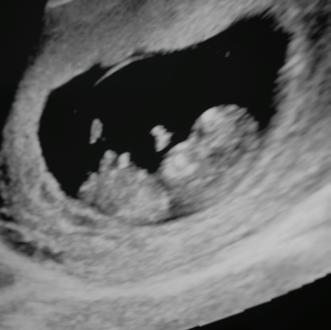

"I couldn't see past me to see them, until I came here." A mom brought her twins back to see the sonographer [pictured] who provided an ultrasound for her when she was considering abortion. She was scared to fly to have an abortion out of state and, after seeing her babies on the ultrasound, she changed her mind and chose life!

Like most clients, this young mom had an emotional response to seeing her baby through an ultrasound for the first time.

• Ultrasound Scans